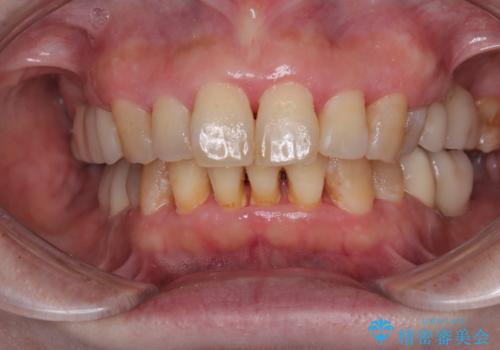

- 上の出っ歯を気にし、矯正治療を希望して美容歯科に行ったところ、ちゃんと説明のないままに前歯がクラウンになってしまったとのことで来院された患者様です。

クラウンとなっても出っ歯はさほど改善されず、更には不適なクラウンであったために歯肉が腫れている状態でした。

まずはクラウンを仮歯に替え、上顎の小臼歯2本を抜歯して矯正治療を実施し、その後歯周外科処置を行った上でオールセラミッククラウンにて補綴することとしました。